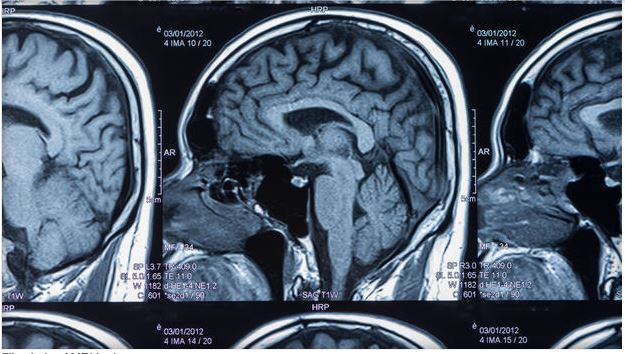

Great article to review: Brain scans may reveal mental secret of "Super Agers"

Great article to review: Brain scans may reveal mental secret of "Super Agers" click on photo to read the article: